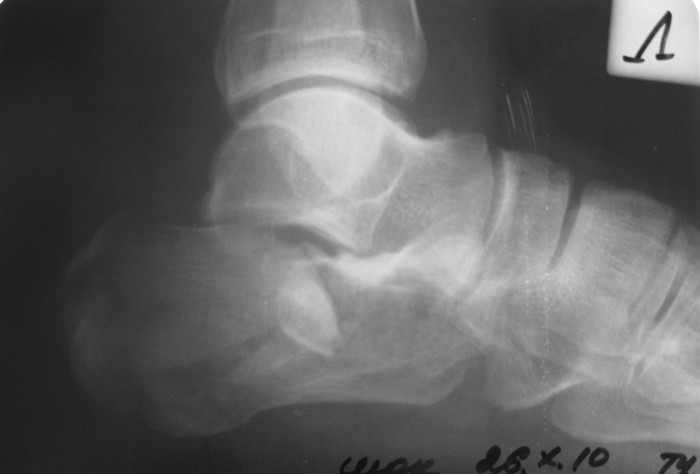

Мужчина, 47 лет. Диагноз: Кататравма (26.10.10г. падение с высоты 2го этажа). Открытый оскольчатый внутрисуставной перелом дистального метаэпифиза лучевой кости, перелом шиловидного отростка локтевой кости левого предплечья со смещением отломков, закрытый оскольчатый внутрисуставной перелом дистального метаэпифиза лучевой кости, перелом шиловидного отростка локтевой кости правого предплечья со смещением отломков. Закрытый оскольчатый внутрисуставной перелом левой пяточной кости, закрытый оскольчатый внутрисуставной перелом дистального метаэпифиза обеих костей правой голени со смещением отломков, закрытый компрессионно-оскольчатый перелом тела L2 позвонка с болевым вертеброгенным синдромом. Голень и предплечья синтезированы АВФ в ургентном порядке. В настоящее время состояние пациента стабильное, к оперативному лечению соматически готов.

Во время клинического разбора мнения разделились: 1) открытая репозиция, МОС пяточной пластиной 2) гипсовая иммобилизация 3) ЧКО аппаратом внешней фиксации как репозиционный и окончательный вариант остеосинтеза. 4) необходимость СКТ?

Коллеги, пожалуйста, интересует ваше мнение относительно тактики лечения,  необходимого перечня рентгенологического обследования оскольчатого внутрисуставного перелома пяточной кости и сроков выполнения предполагаемой операции. Просим высказаться относительно необходимости выполнения СКТ как важного этапа диагностики.